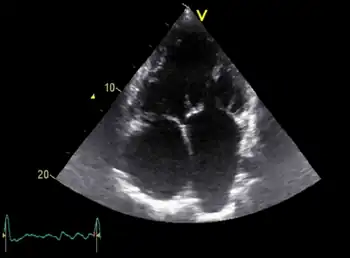

Diagnosis of Eisenmenger syndrome is typically conducted via transthoracic echocardiography, which facilitates the identification and evaluation of shunts, anatomical defects, and ventricular function. Following diagnosis, or in some cases of inconclusive diagnosis, a cardiac catheter may be used to both confirm the diagnosis and to assess the patient's pulmonary arterial pressure, an important predictive value for prognosis and treatment.[8]